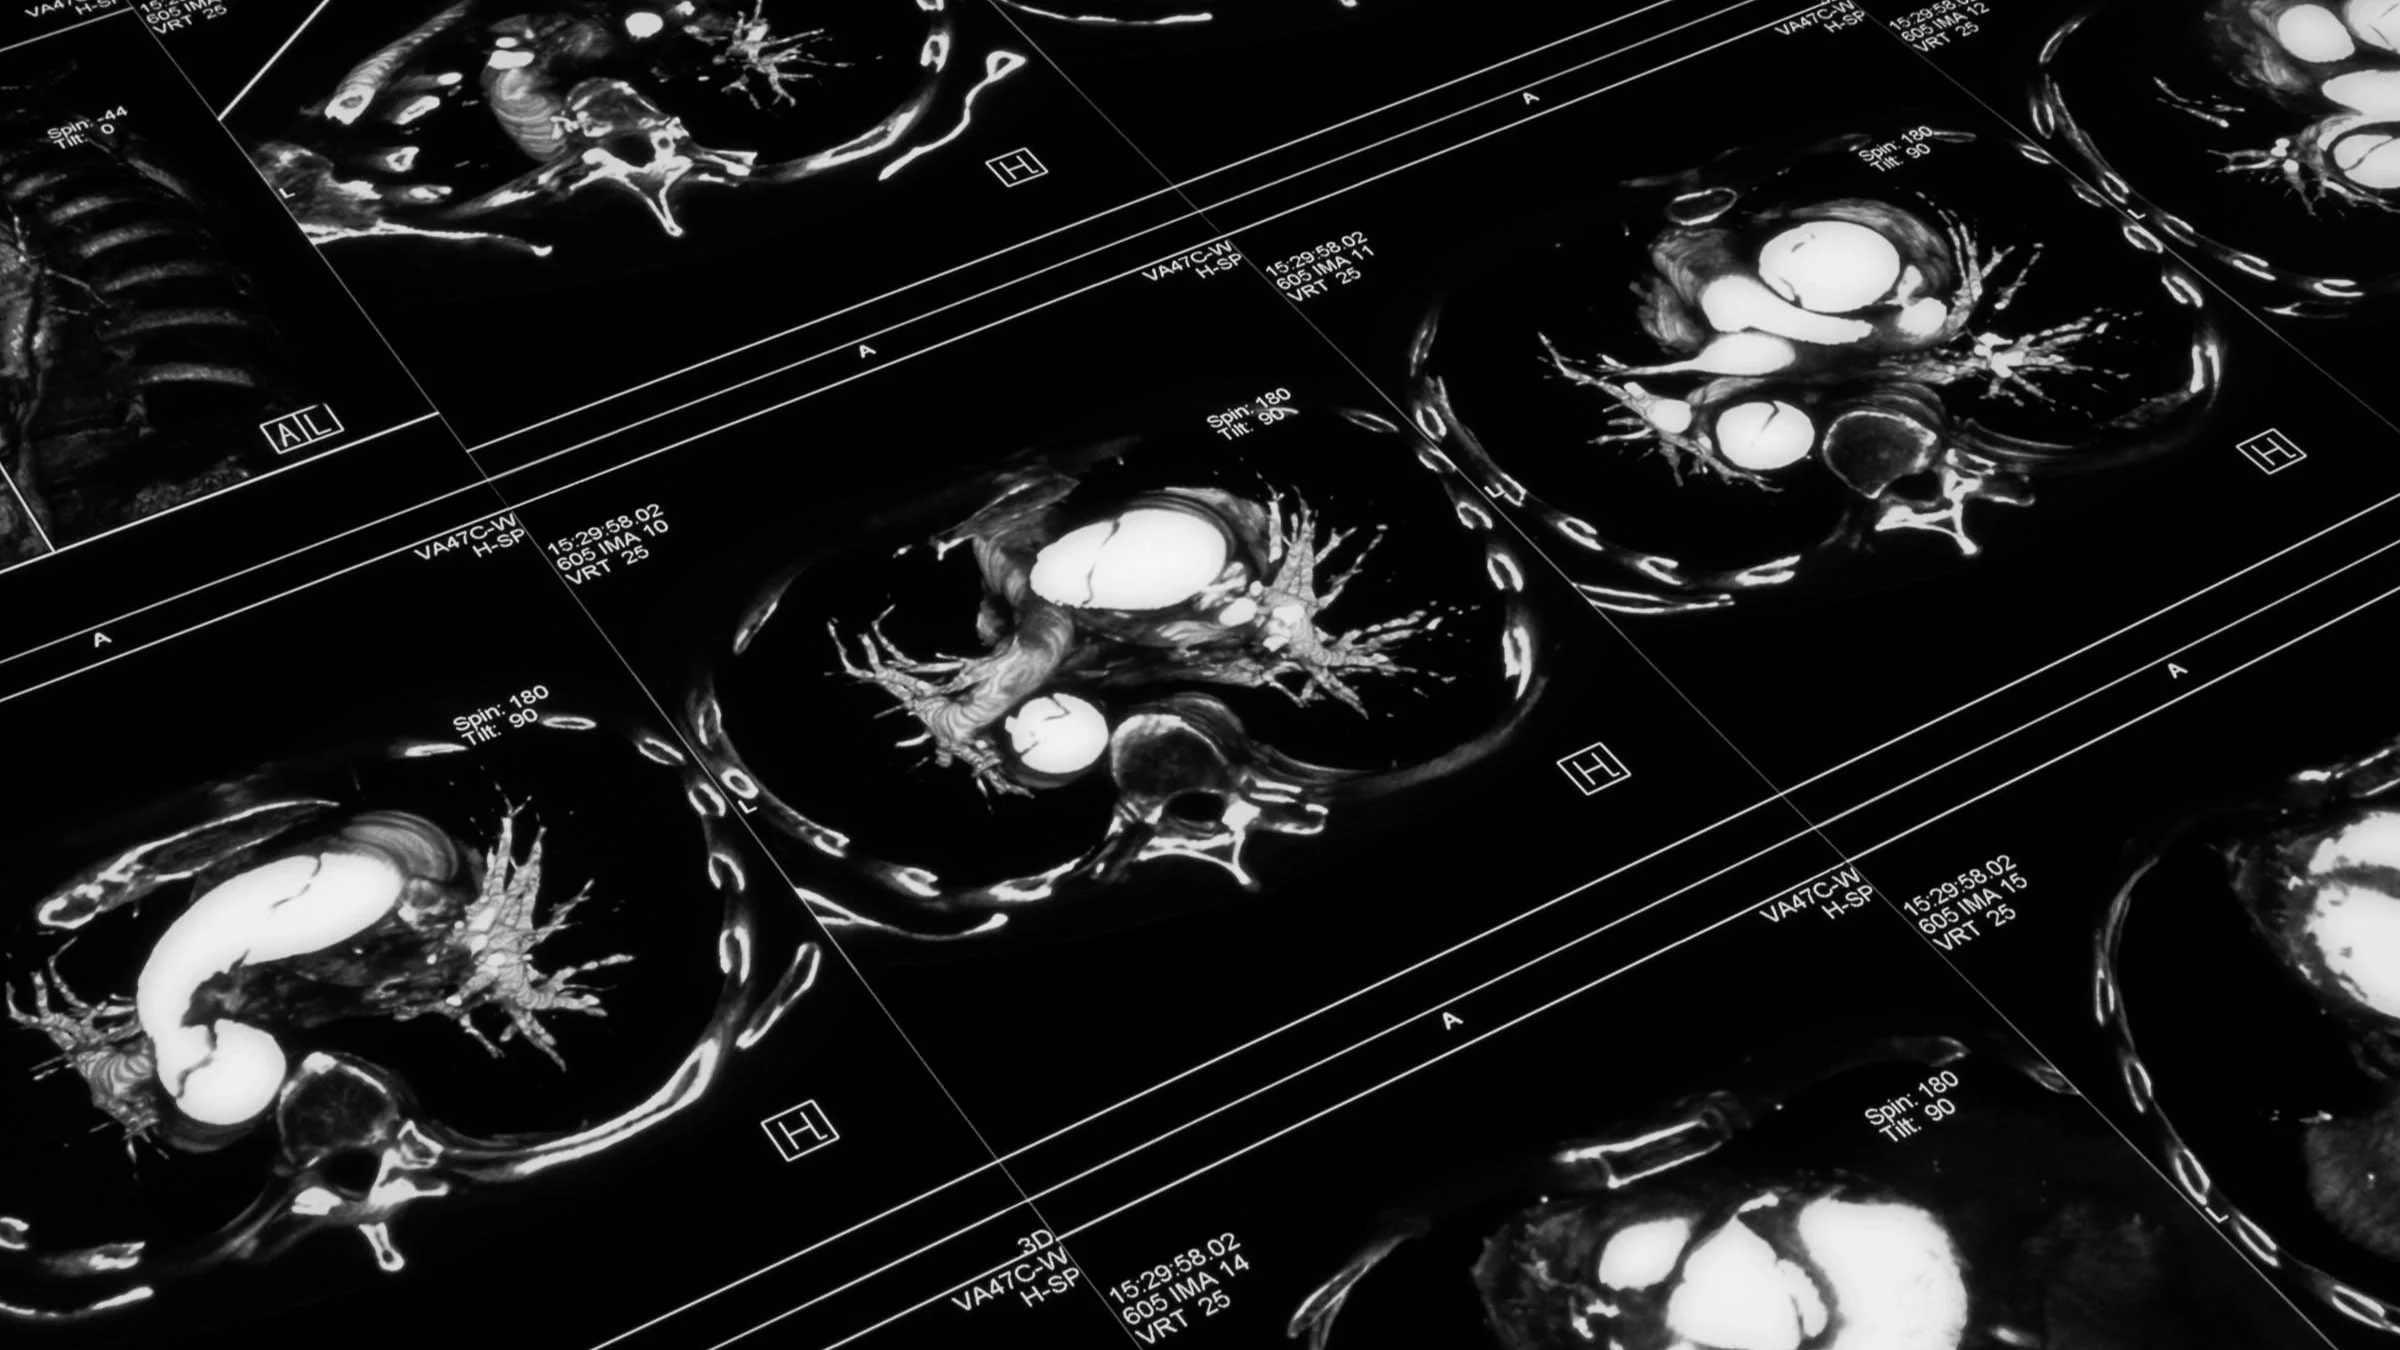

Aortic aneurysms

The aorta is the major artery that carries blood from the heart to the rest of the body. It travels through the chest (or thoracic cavity) and down into the abdomen, finally branching off into smaller arteries in our pelvis that supply blood to our legs.

There are two types of aortic aneurysms:

1) Abdominal aortic aneurysms are more common in men over age 65. They involve the part of the aorta that’s located in the abdomen.

2) Thoracic aortic aneurysms are less common. They involve the part of the aorta located in the chest above the diaphragm.